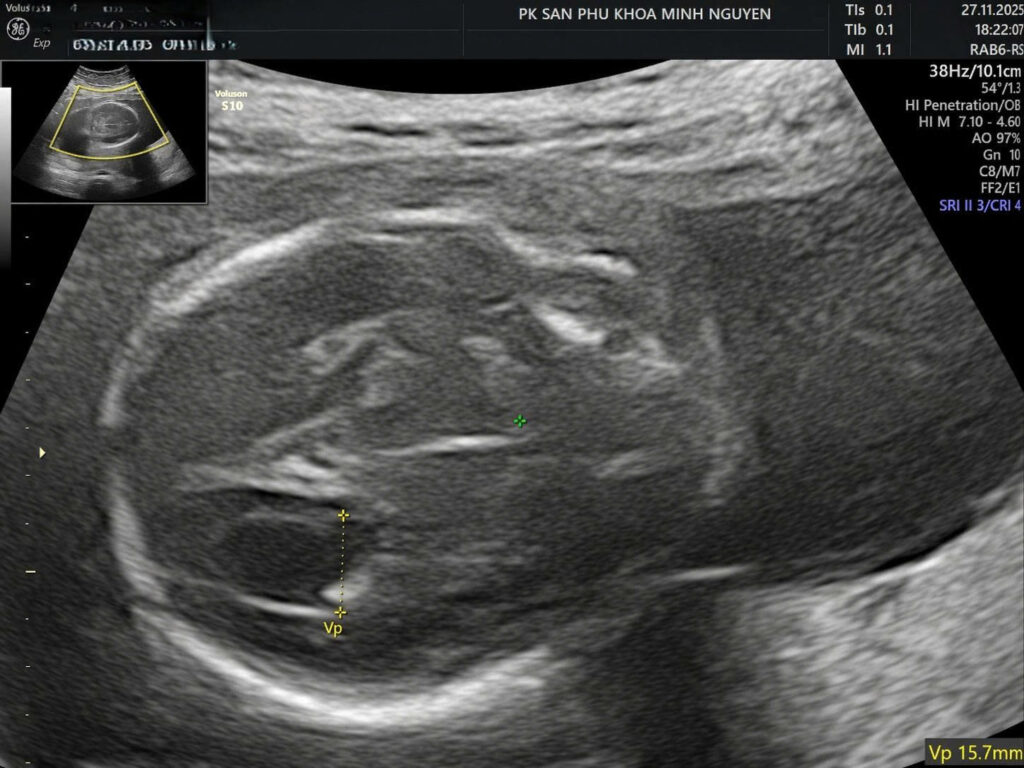

Giãn não thất là tình trạng não thất bên giãn từ 10 mm trở lên. SMFM chia thành nhẹ 10 đến 12 mm, vừa 13 đến 15 mm và nặng trên 15 mm. Đây là một dấu hiệu siêu âm, không phải là chẩn đoán nguyên nhân cuối cùng.

Khi não thất giãn nhiều và kéo dài. Nhu mô não xung quanh có thể bị chèn ép và biến dạng. Trên lâm sàng, nguy cơ bất thường kèm theo và nguy cơ kết cục xấu tăng khi mức giãn tăng lên. RCOG cũng ghi nhận MRI có thể cho thêm thông tin về độ dày vỏ não và mô hình nếp cuộn não trong các trường hợp nghi ngờ bất thường thần kinh trung ương.